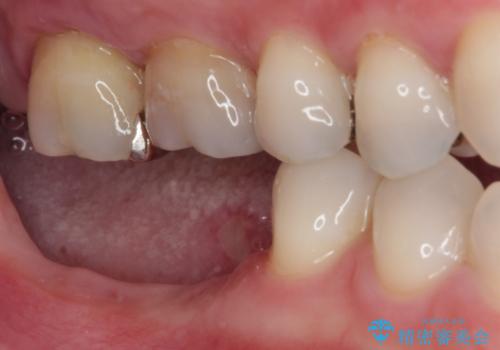

不正咬合で抜歯となった奥歯 インプラントによる咬合回復

- 近医にて抜歯が必要と言われたとこのことで来院された患者様です。

歯周病により抜歯が必要と診断されたとのことでしたが、実際は奥歯以外に歯周病の所見はなく、不正な咬み合わせにより負担が過剰となり、歯を支える歯槽骨が吸収している状態でした。

歯の周りの炎症が顕著であったため、抜歯後炎症が治まるのを待ち、咬み合わせが改善できる位置にインプラントを埋入することとしました。

長年の咬合により、周囲の奥歯がすり減っているため、よりインプラントが長い期間安定するよう、睡眠時にはマウスピースを装着することを強く推奨しています。